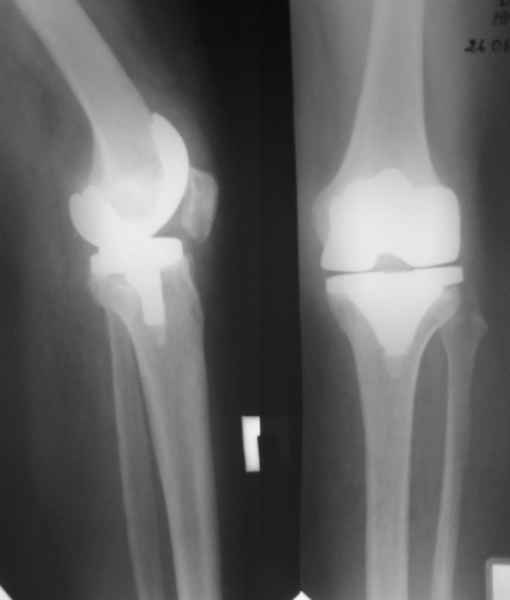

Уважаемые коллеги, Прошу совета. В феврале 2007 года пациентке выполнено эндопротезирование коленного сустава.

13/02/07 |  25/07/07 |  дек. 07 |  25/06/08 |  14/01/09 | Через 1 месяц после операции объем движений 90 градусов, через 2 месяца 60, через 3 - 40, через 5 - качательные движения.

В июле 2007 года выполнена ревизия - полости сустава нет. Капсула сустава имеет толщину от 1 до 1.5 см, собственная связка надколенника имеет толщину до 3 см. Сустав заполнен фиброзно-рубцовой тканью. Компоненты стабильны.

Есть вопросы к установке протеза. Скорее всего тибиальное плато было не конца резецировано и в задненаружных отделах осталась ступенька. Это привело к тому, что тибиальный компонент завалился на варус.

Ты мне говорил об этом случае, а теперь я увидел снимки. Для исключения или подтверждения гнойного процесса надо взять обязательно посев. По-моему и бедро шатается. Ревизовать при ислючении гнойно-септических осложнений надо полностью либо CCK комплектом или связанным.